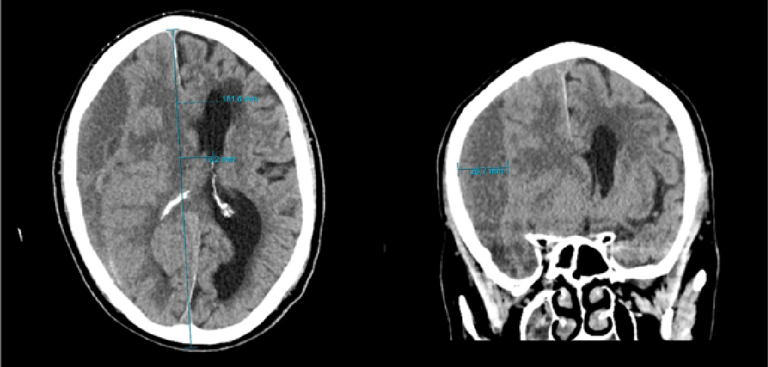

The patient, a 74-year-old man was admitted to the Queen Ingrid's Hospital in Nuuk with worsening dizziness, persistent tendency to fall, and headache following a minor head trauma approximately 2 months prior to admission. CT imaging of the cerebrum reveals a right-sided chronic subdural hematoma causing compression of the entire right hemisphere and the lateral ventricles. The hematoma measures 26.7 mm at its broadest point, resulting in a 20 mm leftward displacement of the midline structures.

A right-sided chronic subdural hematoma with mass effect and midline shift was identified. The procedure, performed by orthopedic resident Dr. Najannguaq Jørgensen, involved creating a burr hole to remove the hematoma and irrigate the affected area.